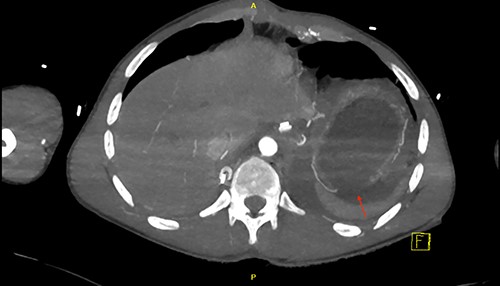

CT scan revealed a large left haemothorax and evidence of left diaphragmatic rupture with herniation of abdominal organs to thoracic cavity such as the spleen, stomach and splenic flexure of the colon; fractured all 12 left ribs, pulmonary contusion, unstable fractures of T6, T10 with acute spinal cord injury (complete transection; Figs 1–3).

Coronal view of CT chest and abdomen with herniation of the stomach and spleen into the thoracic cavity.